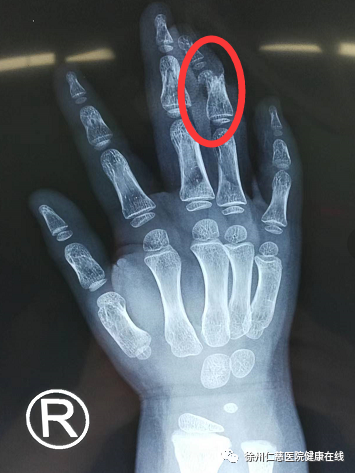

「儿童断指再植的难度要比成人更大。」徐州仁慈医院手外科二病区熊祖国医生说,儿童年龄小,手指上每根血管的直径约 0.4-0.6 毫米,比成人更细。

手术是在显微镜下进行,五岁小孩的指侧血管直径不到 0.2 毫米,2 小时的手术过程中,手术视野的直径也不过 5 公分,缝合用的线比头发还要细得多,非常考验医生的细致与耐心。